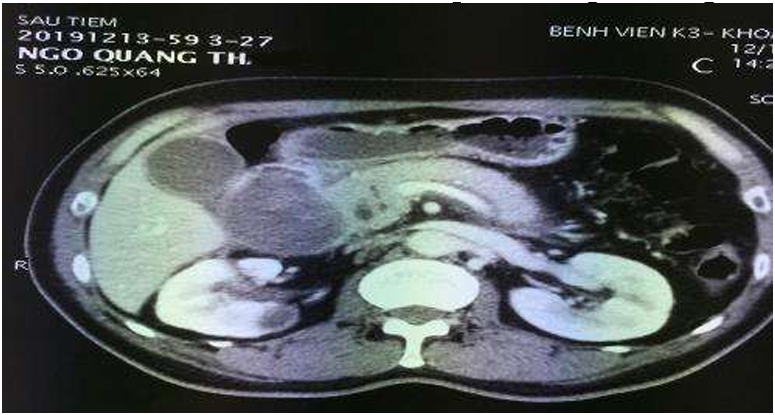

3.4.3. Chụp CLVT Bụng có tiêm thuốc cản quang

- Có giá trị trong chẩn đoán, nguyên nhân , giai đoạn và nhất là trong ác tính